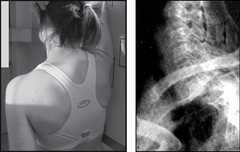

THORACIC SPINE

image

Projection: AP

Centring Point: To a point 5 cm below the suprasternal notch

Projection: LATERAL

Centring Point: To a point 5 cm anterior to the palpable sixth spinous process

Points to consider

Technique

image AP – use a wedge filter to prevent the upper thoracic vertebrae being over-penetrated

image Flex the knees to aid the patient’s comfort

image AP – exposure on arrested inspiration

image Lateral – a long exposure with gentle breathing to blur the lung fields and ribs (diffusion technique)

Radiological assessment

image AP – abnormal soft tissue enlargement around the spine is a positive indication of trauma or infection

image Check all pedicles are present and intact

image Vertebral bodies should be the same height – anteriorly and posteriorly

image Lateral – upper spine difficult to visualise due to shoulders. A swimmer’s projection may be required – CT is better

AP

Patient supine

Median sagittal plane perpendicular to the cassette

A small pillow supports the head

Patient’s arms are placed down by the side

Collimation

To include: SUPERIORLY: Body of C7

INFERIORLY: Body of L1

LATERALLY: Transverse processes and soft tissues

Lateral

Patient lying on their side

Median sagittal plane and the spine are parallel to the table top

Arms are raised and placed onto the pillow

Knees are flexed and a soft pad is placed between them for comfort

To include: SUPERIORLY: Upper thoracic spine

ANTERIORLY: Vertebral bodies

POSTERIORLY: Posterior rib cage